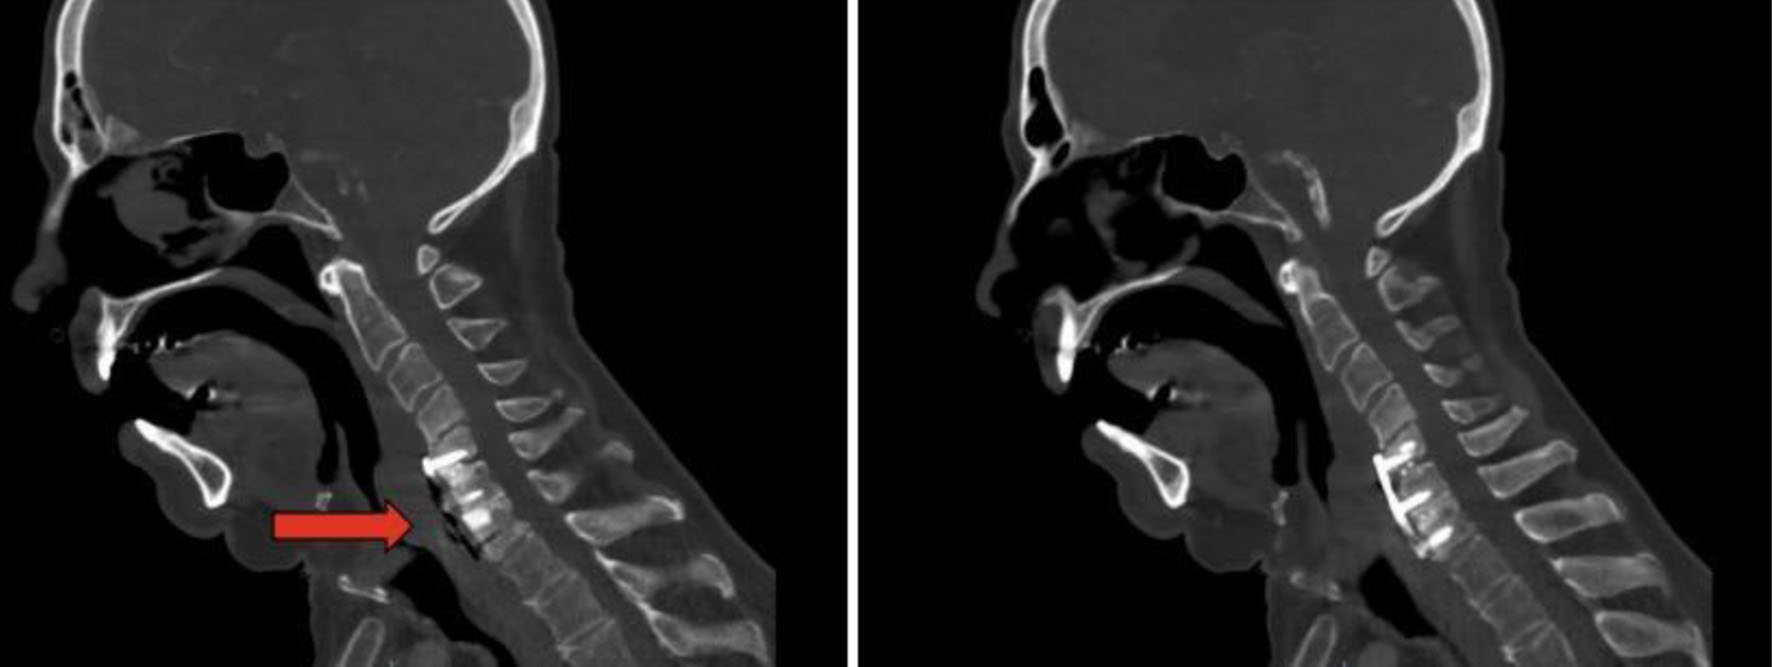

After 6 more months of persistent dysphagia and weight loss without a diagnosis, the patient presented to our network for further workup and treatment recommendations. CT of the neck 12 months postoperatively showed anterior cervical plate in adequate position with air between the plate and esophagus (Fig. 2). An upper endoscopy was performed at 12 months postoperatively, which showed fistulization between the esophagus and the metal hardware in the cervical spine. An esophagram was also performed, which demonstrated no obstruction but decreased peristalsis of the lower esophagus and lateral rightward deviation of the left upper cervical esophagus with minimal mucosal irregularities. Esophagram also showed involvement of the posterior wall of the cervical esophagus overlying the anterior plate and screws without evidence of leak or fistula (Fig. 3).

![]() Click for large image | Figure 2. Computed tomography of the neck 12 months postoperatively. Anterior cervical plate in adequate position with air between the plate and esophagus. |

![]() Click for large image | Figure 3. Esophagram at 12 months. Red arrow indicates defect. The image shows contiguity between the lumen of the esophagus and the cervical hardware based on the transit of the oral contrast, consistent with a posterior esophageal wall perforation contained by the cervical hardware without extravasation. |